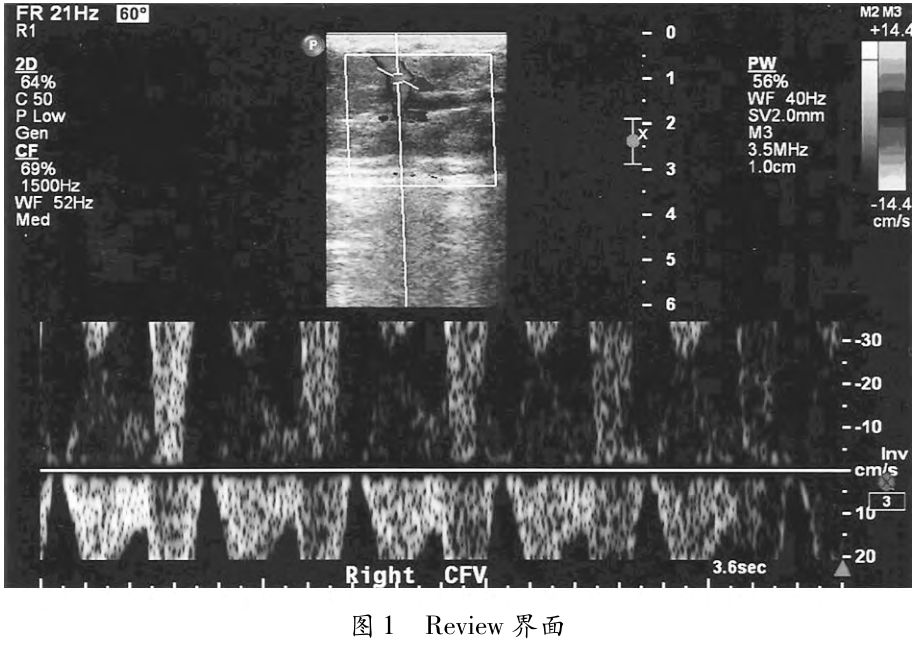

使用中间歇性死机,并带有报错200,报错后on/standby无法使用,直接关电源重启后能正常使用。重新刷SIP和DSC软件,正常使用几天后问题再次出现。查看系统错码,提示DSC的问题:提示信息是数据刷新发生超时。根据这一报错信息,怀疑是DSC方面的故障,但是需要确认这条报错信息是本次系统出现问题的根源。查阅报错的最初信息,提示的内容并不是DSC:这种报错信息问题在于Dolphin的通讯上,继续查看日志:提示的问题指向了Node ID4,也就是HOST的Dolphin板。更换HOST的dolphin卡以及IPL线,并重装软件,故障排除。602报错多数是由于内存导致:内存与插槽之间松动,或者内存金手指表面氧化或脏污,导致的接触不良。首先排除由于BIOS里memory hole设置不当而导致的602报错(使用FII Instruction,确认一下当前软件版本的Hard-ware/Software memory hole的正确设置)。之后清洁并重新固定内存,设备正常启动,故障排除。设备无法启动,停在“initializing hardware”界面,或者启动过程中报错606。主板电池没电,BIOS设置会自动跳到Default Settings,这会导致HOST或SIP启动异常。主板电池的寿命约为5年,用万用表测量电池的电压,低于+2.85Vdc,更换主板电池(HOST/SIP主板用的电池型号为CR2032,UMB/EMB主板用的电池型号为CR2450),并更改BIOS设置到Philips Settings,故障排除。在Review界面下,病人信息的右侧会出现一个红叉标志,在打开的图像中,右下方也会有一个相应的红叉(如图1所示)。是数据文件损坏引起,出现红又的检查将无法输出,但该病人检查内没有红又的图像可以单独输出。调用后台Reset Patient Data-base程序,解决故障。从外部media导入至i正33内的图像,无法以任何格式再次导出。问题原因是系统不允许导出”Imported”的检查。打开导入的检查;双击第一幅图像,至全屏模式;按下i正33上的Acquire键,这样会Append该检查;之后,打开每一幅导入的图像至全屏,按下正33上的Acquire键,这样可将图像拷贝至新的Append检查下面;关闭Re-view;打开Review界面,选择appended study,之后选择Send to Media,即可导出;打开检查后也可以用Jpeg/AVI格式输出,问题解决。探头无法完全的接到设备上,从而导致晶振信号丢失或其它图像质量问题(如图2所示)。探头接口内固定用的内六角螺丝滑脱(如图3所示),探头无法充分与机器上的探头接口模块连接。使用英制3/32内六角工具,固定螺丝。机器使用过程中出现图像不同步(图像延迟,开始每两三天出现一次),同时偶尔会有EHA206报错。之后每天都出现图像延迟的现象。关机重启之后就好了,可是坚持不了太长时间就又会出现。查看故障日志,所有的报错都指向SIP。重点排查SIP,首先把SIP上Dolphin的PCI接线插拔把SIP上的板卡插拔观察,故障依旧。然后把SIP和HOST的Dolphin互换,故障仍在。经过几次操作发现SIP的一个CPU风扇响声有时不正常。再仔细观察发现风扇转速也时而不正常。再次查看Log 选中Temperature 发现SIP/CPU的温度过高了达到了82℃(正常应该在45℃左右),所以导致了SIP的处理功能下降,出现了图像的延迟现象。更换CPU的风扇和SIP,风扇温度恢复正常,故障解决。在对IE33超声诊断仪维护的过程中,逐步积累一些经验和体会,日常维护中按时清洁保养,每季度清洁过滤网,每年对设备除尘。设备运作正常时记录好设备启动、工作、关闭时的工作点电压等重要参数,对及时定位排除故障很有用。[参考文献] [1]石用伍.飞利浦IE33型B超的日常保养与故障检修[J].医疗装备,2011,24(03):79. [2]赵明.PHILIPSiE33彩超数据恢复维修案例[J].医疗装备,2009,22(05):59. [3]秦占伟,郑盘根,诰宝成,飞利浦iu22彩超影像工作站影像采集故障检修分析[J].中国医疗设备,2010,25(12):120,134. [4]马莉,张福军,孙伟才等,飞利浦iU22彩色超声诊断仪故障分析[J].临床医学工程,2011,18(05):772-773. [5]史文兵.飞利浦彩色超声iU22维修一例[J].医疗装备,2009,22(09):59. [6]苏燕平,朱建.飞利浦lU22彩色超声诊断成像仪故障维修[J].中国医疗设备,2010,25(02):105. [7]张荣和.飞利浦IU22超声诊断仪无法进入系统故障的解决[J]临床医学工程,2010,17(07):141-142.